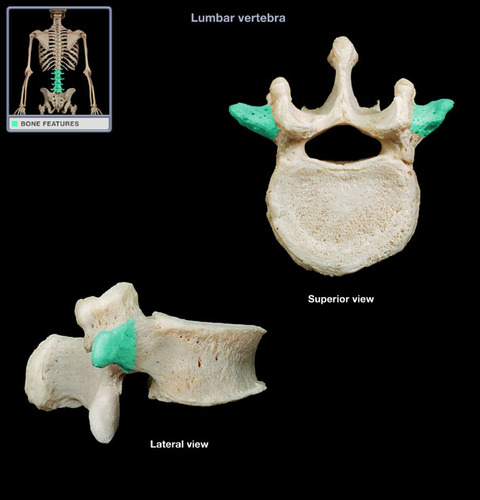

lumbar vertebrae